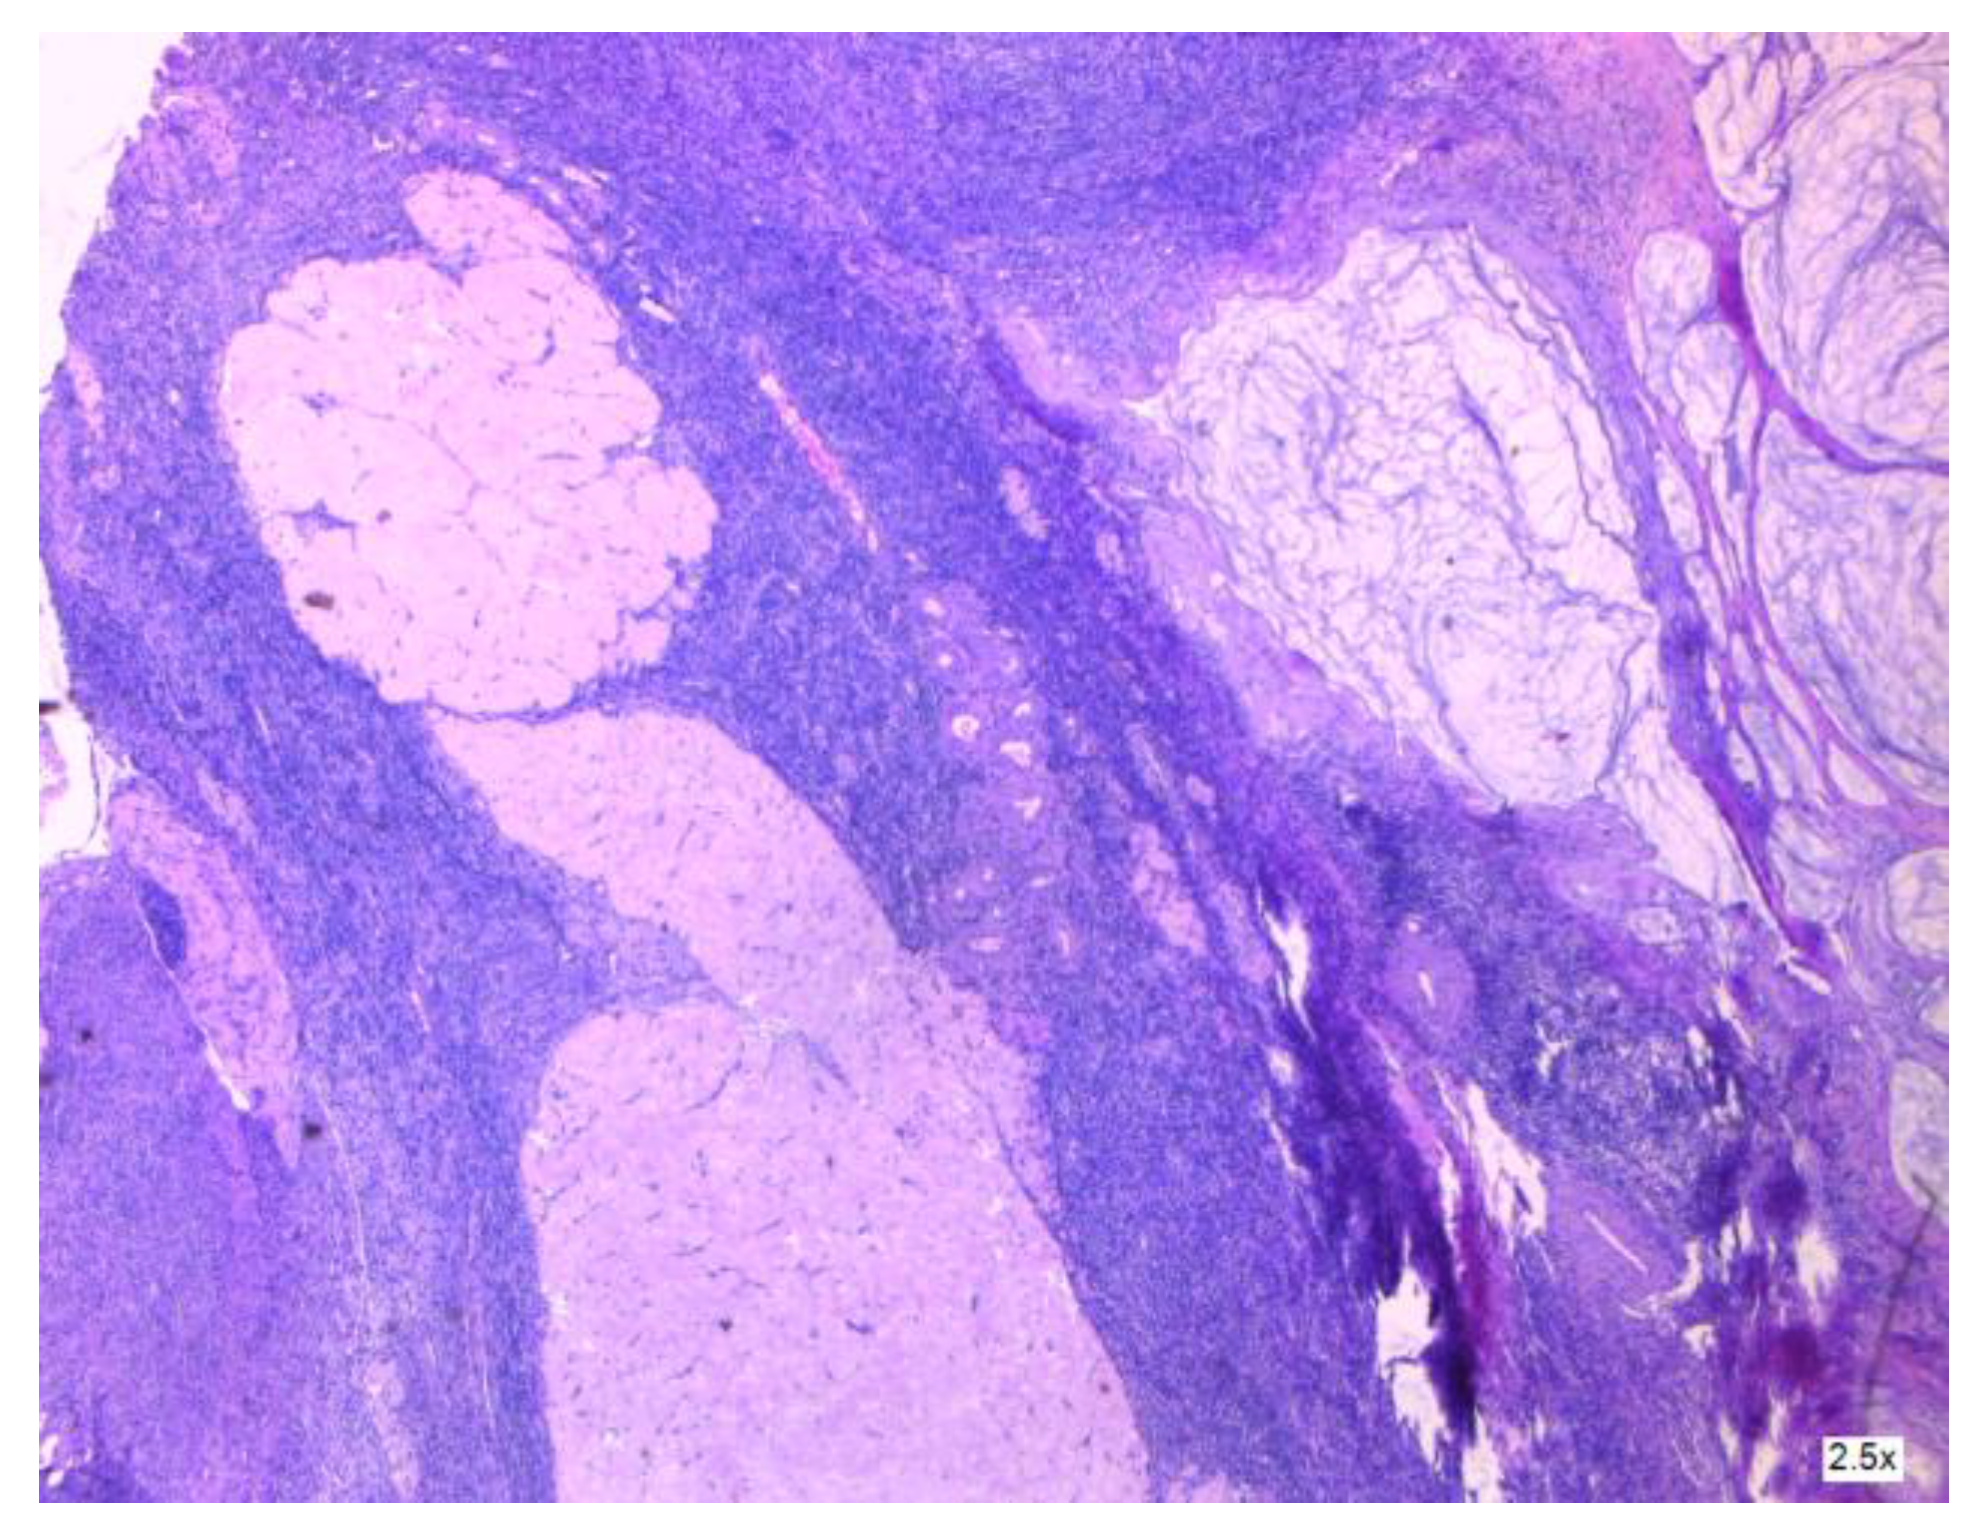

3.2.2. Clinical and Pathology Findings

- Dundr, P.; Singh, N.; Nožičková, B.; Němejcová, K.; Bártů, M.; Stružinská, I. Primary mucinous ovarian tumors vs. ovarian metastases from gastrointestinal tract, pancreas and biliary tree: A review of current problematics. Diagn. Pathol. 2021, 16, 20. [Google Scholar] [CrossRef] [PubMed]

- Hegg, K.S.; Mack, L.A.; Bouchard-Fortier, A.; Temple, W.J.; Gui, X. Macroscopic and microscopic characteristics of low grade appendiceal mucinous neoplasms (LAMN) on appendectomy specimens and correlations with pseudomyxoma peritonei development risk. Ann. Diagn. Pathol. 2020, 48, 151606. [Google Scholar] [CrossRef]